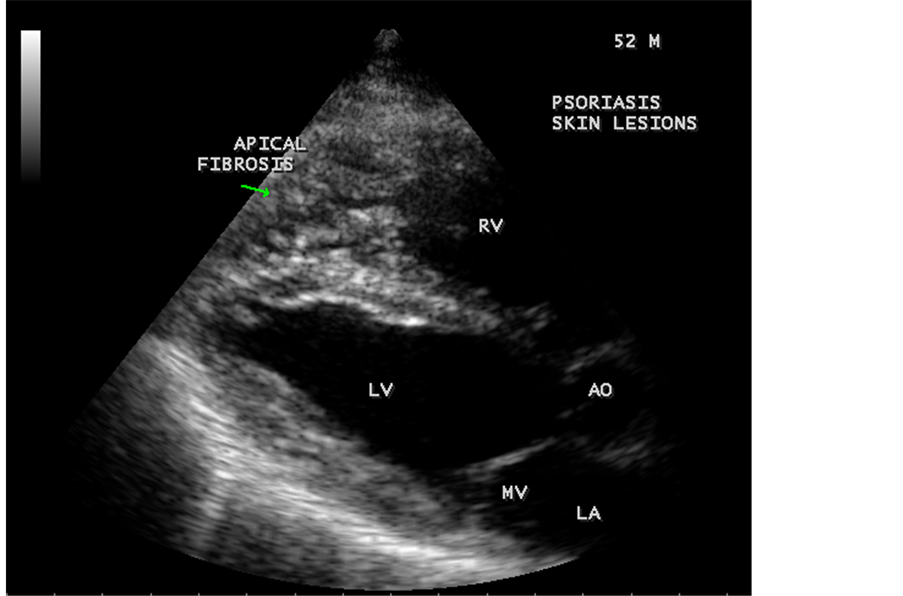

Transthoracic echocardiography revealed strong fibrous strands appearing as “finger like projections” or “cobra-head” appearance in the right ventricular apex due to fibrosis of muscular trabeculae, suggesting right ventricular endomyocardial fibrosis as shown in Figure 3 to Figure 7.

Figure 5. Parasternal long axis view showing the RV (right ventricular) apical fibrosis in a 52-year-old male with psoriasis.

3.3. Echocardiographic Features

Today echocardiography is used as the screening tool at the community level as the diagnosis of EMF could be confirmed at the bedside. Echocardiography accurately assesses the pathological abnormalities of chronic disease and it is the gold standard technique for the diagnosis of EMF [36] . It reveals dense endomyocardial echocardiograms along different parts of the mural and valvular endocardium and AV valve dysfunction [37] as shown in Figure 3 to Figure 7, Figure 10 to Figure 15, Figure 17, Figure 18, Figure 20 to Figure 75 and Figure 78 to Figure 84. The typical feature of EMF is the obliteration of trabecular portion of the ventricle and in advanced cases, there is shrinkage of the cavities creating an apical notch, regurgitation, slow flow with spontaneous echo contrast as in Figure 36 and considerable pericardial effusion. Similar to apical notch of right ventricle, a right atrial notch is well seen as contraction (or retraction) of tricuspid annulus as in Figure 41 and right atrial notch as in Figure 42 and Figure 43, indicating the retraction of right atrial cavity as a peculiar feature of right ventricular EMF. Biventricular enlargement as shown in Figure 41 and biatrial